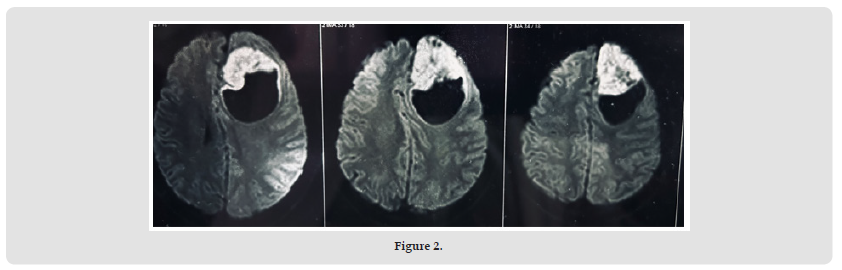

A 24 years old male was referred to our centre with history of headache for last 1 month and 3-4 episodes of vomiting and blurring of vision for 5-10 days. Detailed history from his family members revealed a change in behavior, including agitation, apathy, irritation from last 10-12 days. There was no history of loss of consciousness, seizures or any limb weakness. On examination, no neurological deficit was detected.The Magnetic Resonance Imaging(MRI) of the brain preoperatively showed a large cyst with mural nodule morphology in left frontal lobe measuring 7.5 x 4.8 x 6.3 cm, with intermediate signals on both T1W and T2W images with mild post contrast enhancement. A significant mass effect was noted with rightward shift of anterior midline structures by 7mm, with compression and distortion anterior aspects of both lateral ventricles. Mild subfalcine herniation was also present. Figures 1-3 shows the pre-operative MRI Brain findings. The patient underwent left frontal craniotomy and decompression of the lesion. However due to some complications patient required re-exploration with left temporoparietal craniotomy and extradural hemorrhage evacuation.